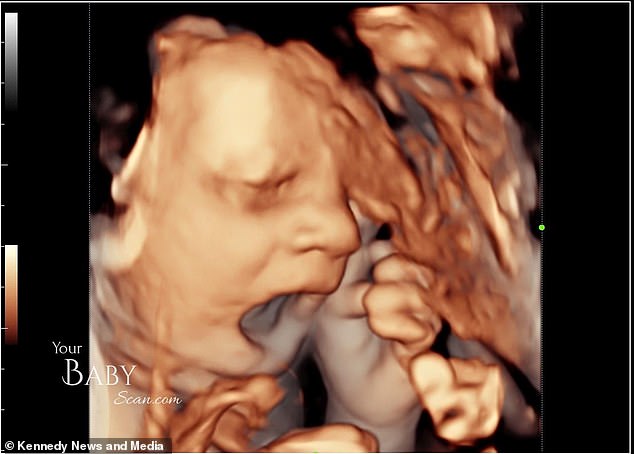

Родители были потрясены, когда их сын показал средний палец. На веселых фотографиях 4D-сканирования видно, как маленький мальчик закрывает лицо, зевает, а затем показывает неприличный жест.

«За пять минут до конца он решил показать нам средний палец, как бы говоря: хватит, мама и папа, оставьте меня в покое», – сказала девушка.

Она добавила: «Мой жених видел это, но не сразу заметил, что произошло. Я и сонографист посмотрели друг на друга и спросили: «Он что, только что показал палец?».